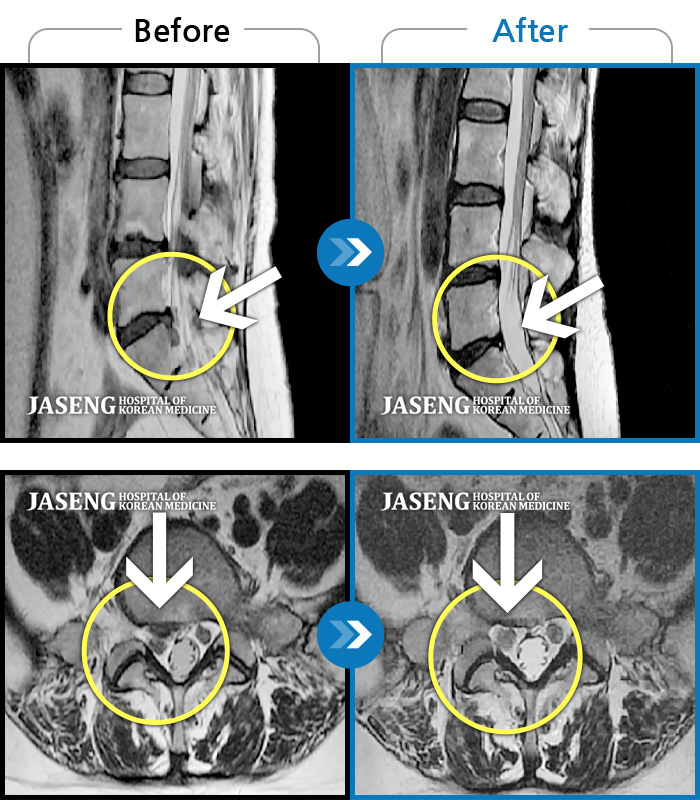

허리디스크

해운대 · 김상돈 원장

허리가 찌릿찌릿하고 찢어질 것 같은 통증

촬영시기

2024.01.08 ~ 2025.08.12

2025.08.29